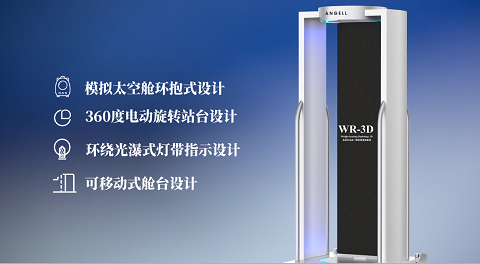

安健科技基于數字化X線攝影技術創新的WR-3D負重位多角度三維掃描系統

安健科技WR-3D負重位動態三維攝影技術